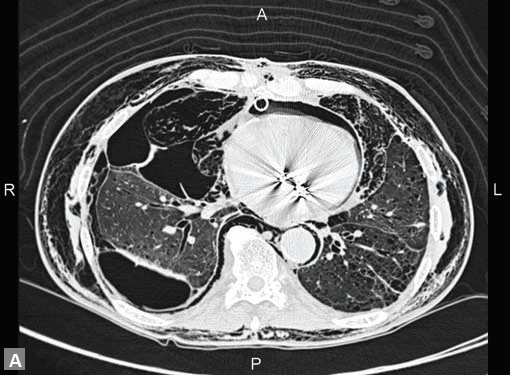

Computed tomography is not preferred mode of investigation in ostium primum and secundum defects and in fact smaller defects are often missed. Secundum type ASD is the most common congenital heart defect to present in adults. Equalization of contrast density in left and right cardiac chambers during the study is an indication of possible shunt lesion.

Primum type is seen as a defect immediately posterior to atrioventricular valves. Primum variety is associated with Down’s syndrome and other congenital anomalies. This type of ASD is a mild form of endocardial cushion defect. Secundum type is the most common variety. Usually defect is large. Associated RA enlargement, dilation of MPA (Fig. 23G) may be noted. Patent foramen ovale (PFO) and fossa ovalis mimic small secundum ASD. PFO is usually a left to right shunt with a tunnel-like appearance. Events that increase RA pressure such as coughing, Valsalva maneuver, tricuspid regurgitation (TR) can cause right to left shunt in PFO. PFO jet is directed to floor of right atrium and roof of left atrium.

Radiologist has a crucial role in suspecting or confirming the diagnosis in next two types of ASD: (1) sinus venous type and (2) unroofed coronary sinus. Superior sinus venous ASD (Figs 23C to F) represents a defect between SVC-RA junction and LA. It is usually associated with partial anomalous pulmonary venous connection (PAPVC) (right upper lobe pulmonary vein draining into SVC). Inferior sinus venous type has a defect at IVC-RA junction and LA. This too can be associated with PAPVC (right lower lobe pulmonary vein draining into IVC or RA). Unroofed coronary sinus,20 the least

common type of ASD is suspected when contrast escapes from inferior aspect of LA to roof of unopacified coronary sinus. A common association is persistent left superior vena cava (LSVC). Four types of unroofed coronary sinus are described. Type 1 is completely unroofed without persistent LSVC while type 2 is completely unroofed with associated persistent LSVC. Type 3 and 4 are when coronary sinus is partially unroofed in mid and terminal segment respectively.